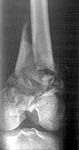

A male 22 years old referred to us from another town. More than 1 month ago (Apr 20) he was injured in a car accident. Among other injuries there was an open distal femoral fracture which hasn't been surgically fixed yet, only traction applied. There are scabs at anterolateral surface over the fracture site even today. No signs of infection though. Fracture mobility is aready limited. What treatment options do you consider for the case? THX in advance.

22 year old 4 weeks after distal femur fracture. Very comminuted metaphysis with some displacement. Intra-articular with some displacement. At least 2 condylar fragments. Most of the comminution appears metaphyseal. Probably grade 2 open soft tissue injury.